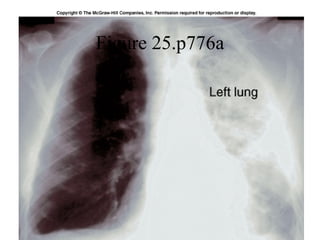

Figure 25.p776a

Note the  base  and the  apex  of the lungs.  Also note that the left lung only has two  lobes , while the right lung has three.

All structures of the respiratory tract beyond the primary bronchi are contained in the lungs.  Note the  right lung  has  three lobes  while the  left lung  has only  two lobes  because of the space taken up by the heart on that side.